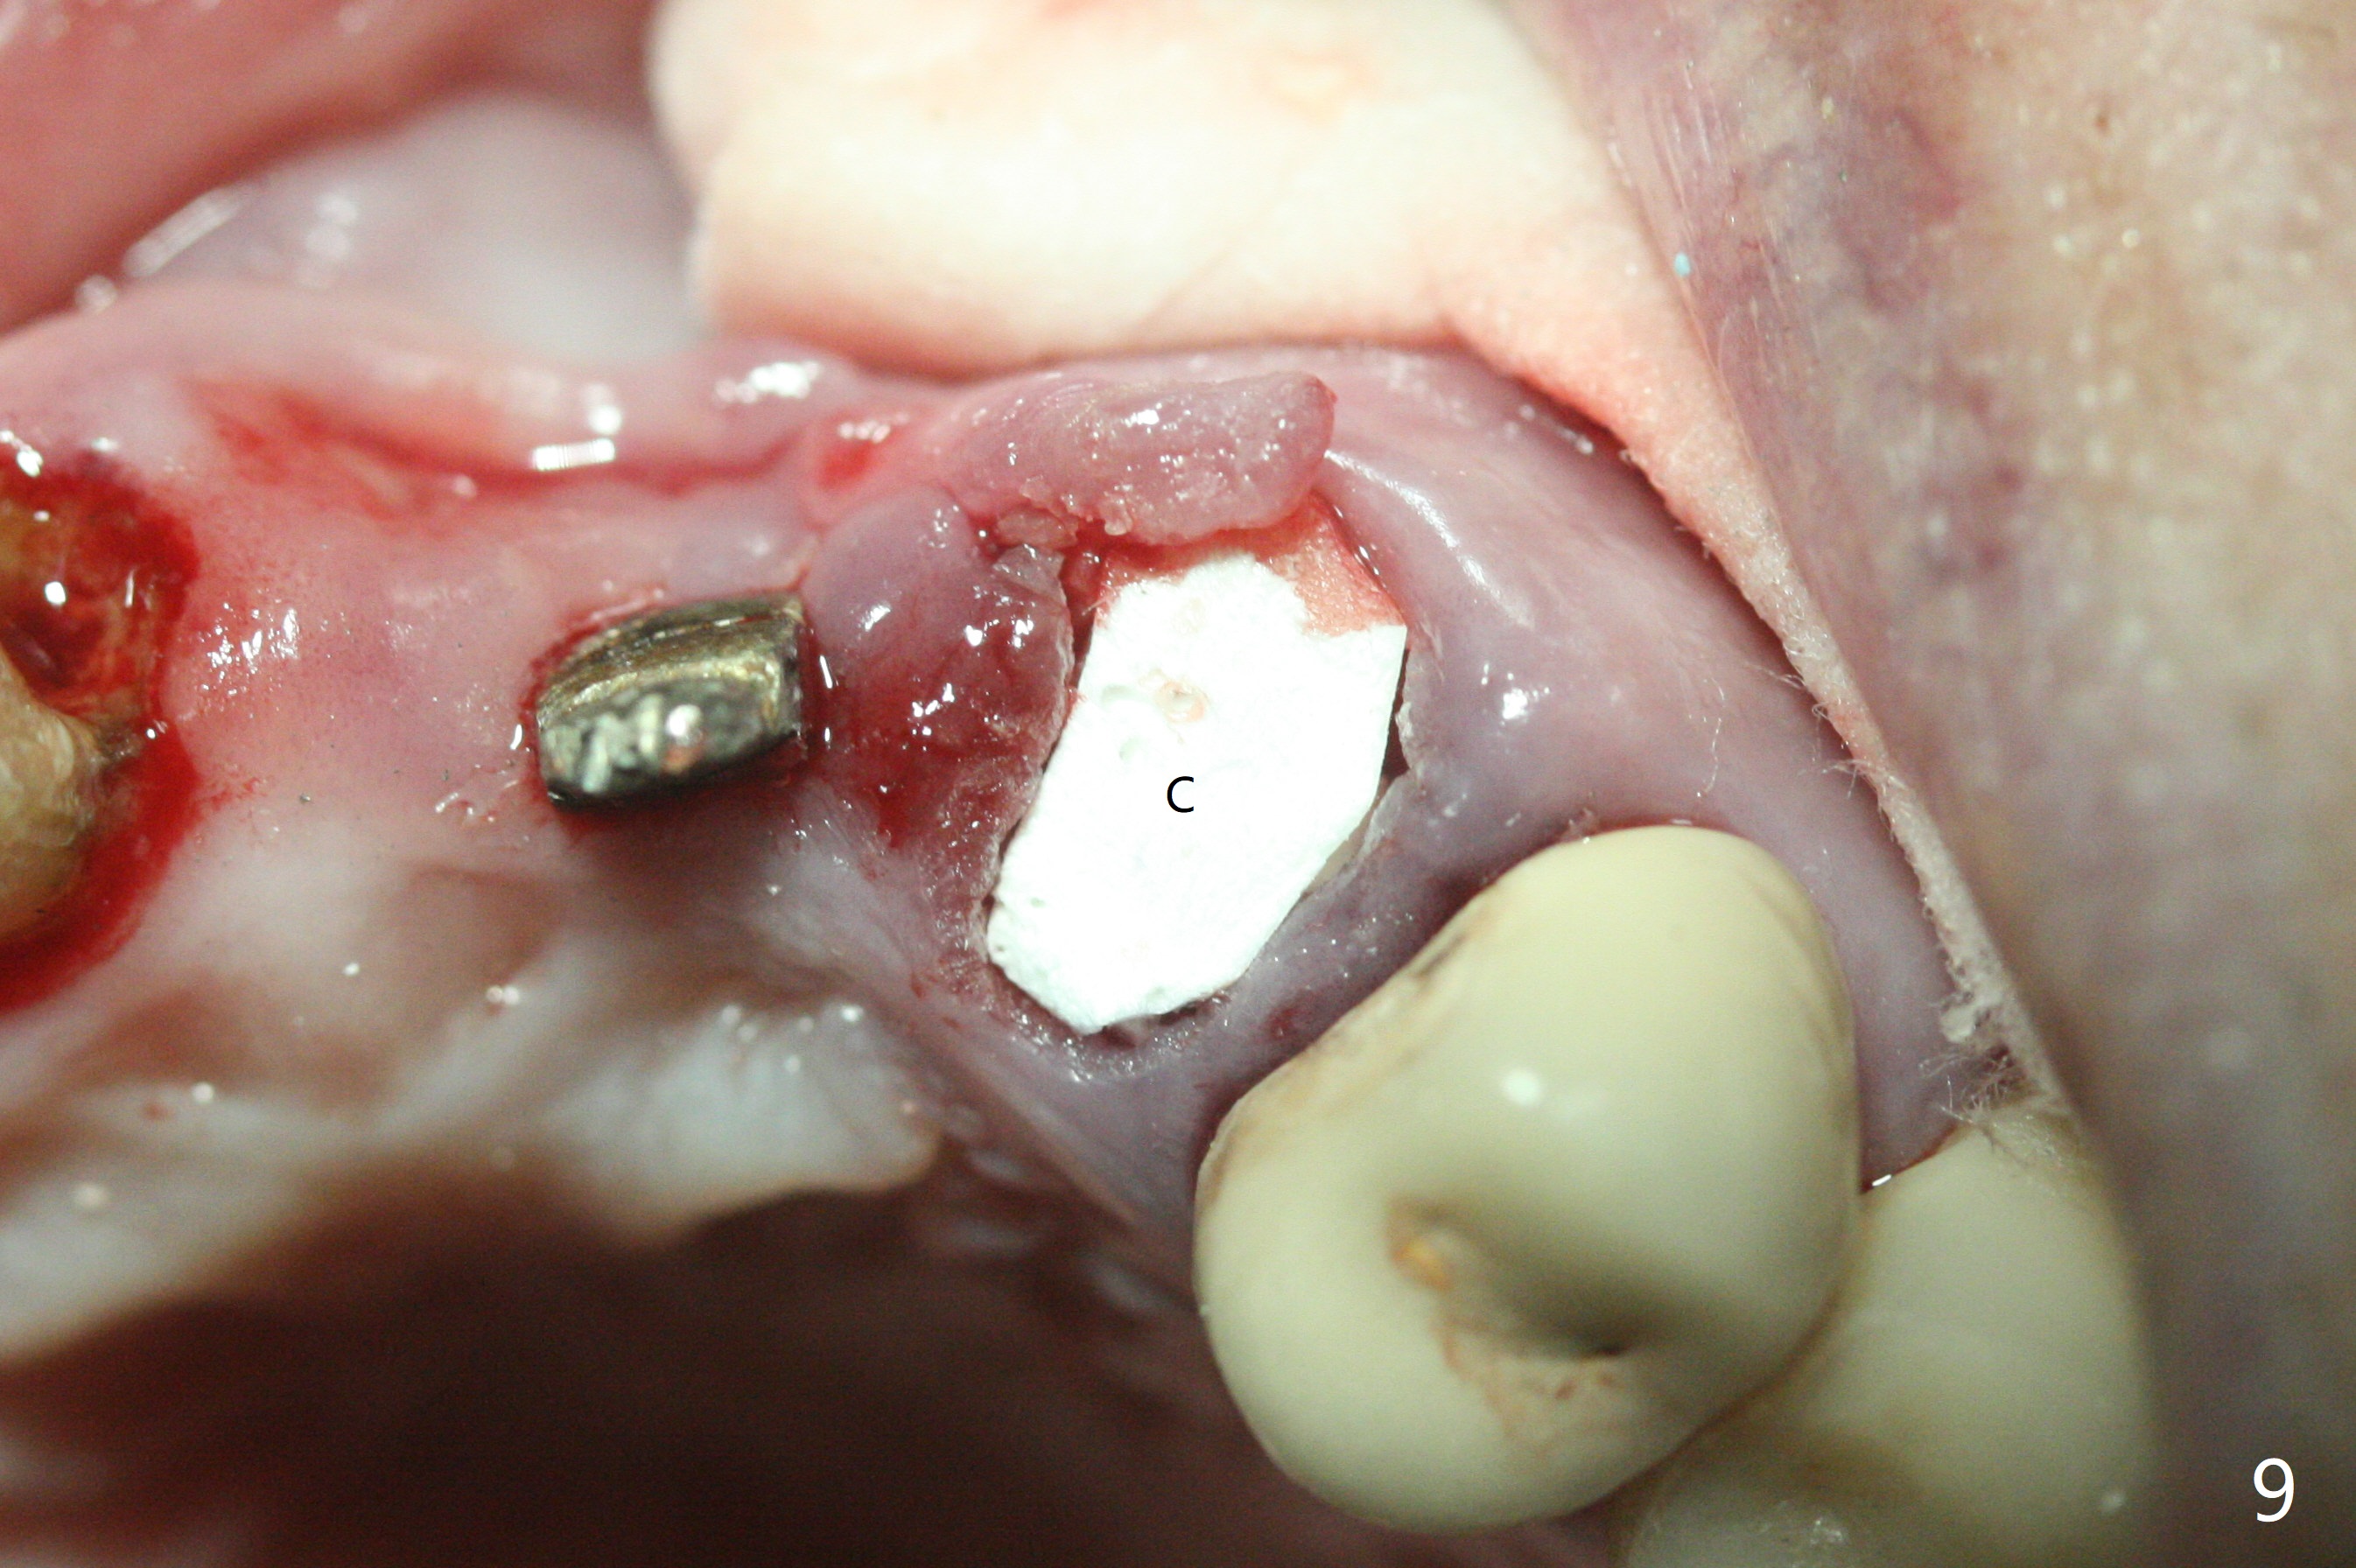

上前牙桥撤除显示右上1,2牙齿以及左上2叶片状植体好像可以保留,而左上3牙齿不能(图一,二(<:托牙边缘压迹)),拔除左上3牙齿后, 暂时把牙桥回位(图三:FPD(已经去除左上3号牙牙冠))作为3号牙种植位置参考(图四至六(G:骨粉))。其实植入前,当最后一个钻头还在原位,将PRF膜和粘性骨放置颊侧根尖(但愿骨粉能放深点),因为那里骨质很薄,好像缺损。由于植体扭力很低(大约5Ncm),放置骨粉覆盖植体(图七),为了不用缝线,涂牙周胶水(图八),放置胶原膜(图九),再涂胶水(图十)固定,最后利用右上1,2号牙(去龋,build-up后)和左上2植体制作临时牙桥,并且覆盖左上3牙槽窝。术后即刻CT显示植体颊侧(B)骨粉(图十一:*)。<:植体根尖仍有间隙,植体应该再长2毫米,初步稳定性会好些。左上3植牙愈合后,将与左上2植体制作左上1-3悬臂桥,右上1,2号牙将做根管治疗,桩,牙冠。临时牙桥术后十一天松动,右上一,二牙牙髓活性测定正常,深洗后,再次build up,不小心把左上3胶原膜吹掉,下面骨粉还稳定。术后三周病人回来做右上六种植,前牙临时修复体(图十二)需要修改(图十三)。拍摄三个方向照片显示前牙牙龈乳头(颊侧和咬合面)。